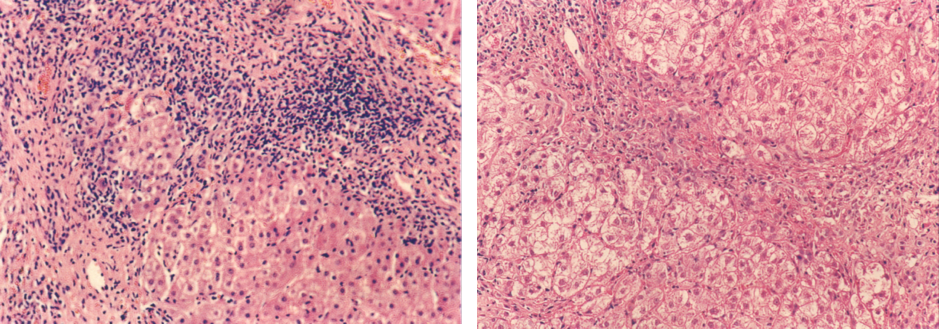

(2)碎片状坏死(piecemeal necrosis):常发生在肝小叶的界板处。镜下见一小群肝细胞发生变性坏死,淋巴细胞和浆细胞浸润,纤维组织增生伸入肝小叶,围绕和分隔单个或小群肝细胞。碎片状坏死是慢性肝炎处于活动期的主要病变。

4.炎细胞浸润 肝炎时在门管区或肝小叶内常有程度不等的炎细胞浸润。浸润的炎细胞主要是淋巴细胞、单核细胞,有时也见少量浆细胞及嗜中性粒细胞等。

镜下见广泛的肝细胞变性,以胞浆疏松化和气球样变最为普遍。肝小叶内可有散在的点状坏死。嗜酸性小体并不常见。由于肝细胞索网状纤维支架没有塌陷,故再生的肝细胞可完全恢复原来的结构和功能。门管区及肝小叶内有少量炎细胞浸润。黄疸型者坏死灶稍多、稍重,毛细胆管管腔中有胆栓形成。

(2)中度慢性肝炎:肝细胞坏死明显,有中度碎片状坏死和特征性的桥接坏死。小叶内有纤维间隔形成,但小叶结构大部分保存。

(3)重度慢性肝炎:肝细胞坏死重且广泛,有重度碎片状坏死,桥接坏死范围广并形成相应的桥接纤维化。可见肝细胞不规则再生。多数纤维间隔,导致小叶结构紊乱,或形成早期肝硬化。